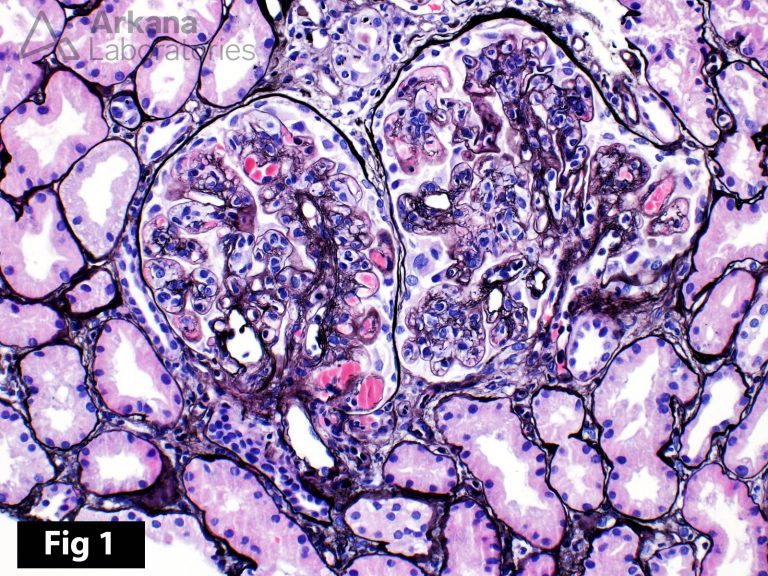

From www.arkanalabs.com

Cryoglobulinemic Glomerulonephritis Teaching Point Arkana Labs Mixed Cryoglobulinemia Histology Web the presence of serum mixed cryoglobulins (mcs) may be an isolated serological finding, the expression of a possible underlying disorder or the. Web we conducted a comprehensive review to evaluate the current status of diagnosis, management, and treatment of. Web mixed cryoglobulinemia (mc), type ii and type iii, refers to the presence of circulating cryoprecipitable immune. Web treatment of. Mixed Cryoglobulinemia Histology.